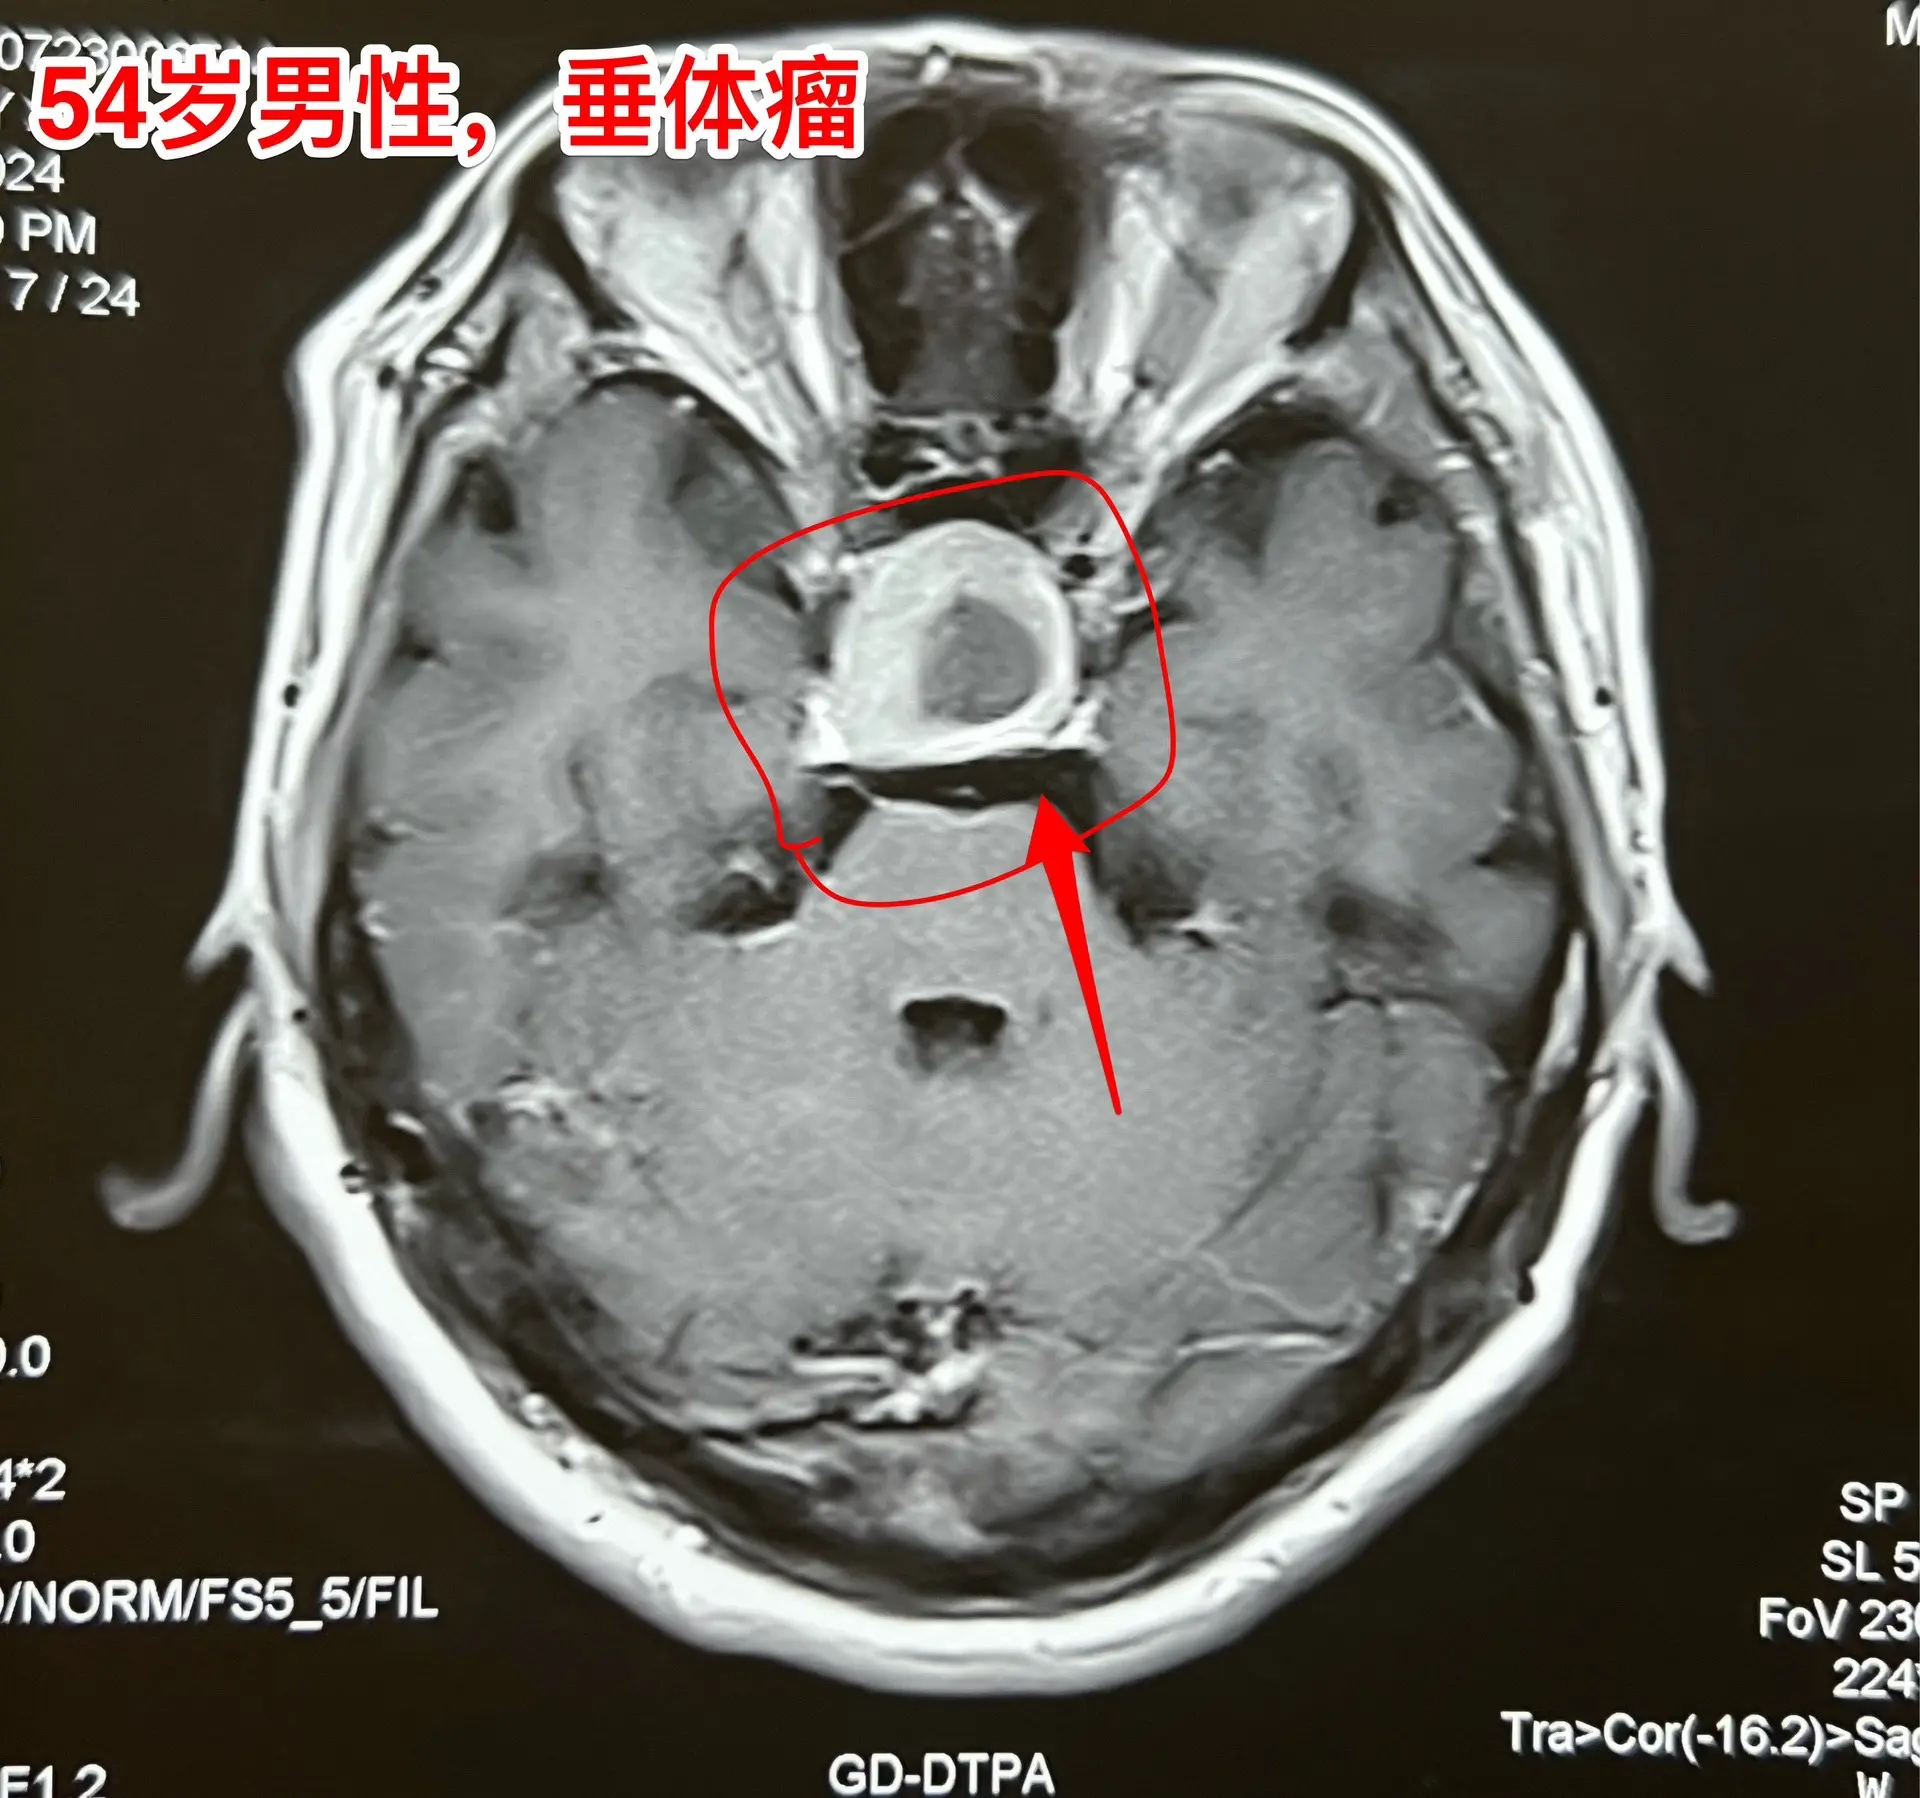

中元节是不是不适合作手术?昨天8月18号是中元节,我们科在上周提前安排在这一天作一台垂体瘤手术,那个时候我还没有想到这一天是中元节。 患者的女儿提到这日子不太好,是中元节,我才意识到的确不太合适。我就说,不行就在8月19日晚上作。这个女儿又说不行,因为8.19是病人的生日!我说如果这样的话只能往后推了,因为前面的手术都排满了。 患者女儿和家人商量了之后还是决定在8.18日作手术,因为之前患者为了排查冠心病,已经耽误了好几天时间,为了能缩短住院时间,他们只好选择8.18这个日子。 患者家属下定决心了,我心里却担心起来了!心里有隐隐的不安和恐惧,但是也不敢告诉病人。 昨天的手术很顺利,手术后我一直在医院等病人完全清醒了,作完了头部CT,结果很满意。在确保病人平安无事了我才敢离开医院。唯恐出现意外! 今天查看病人,病人精神好,自诉视野缺损情况有改善。我彻底放下心来了!